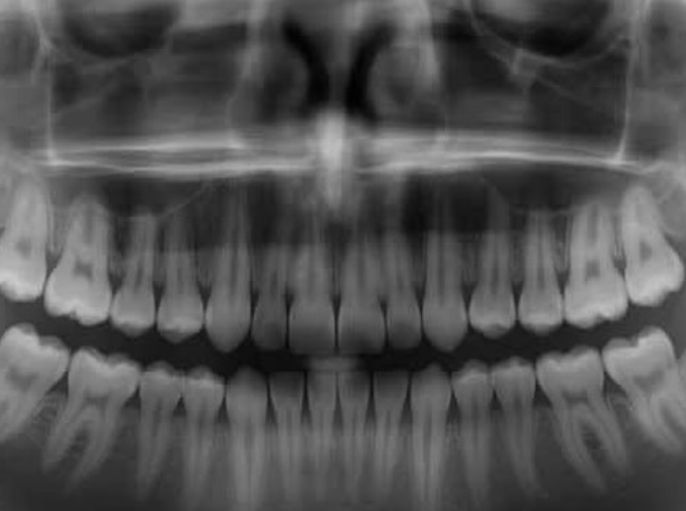

Em experimentos com roedores, o bloqueio dessa proteína resultou no desenvolvimento bem-sucedido de novos dentes completos. Agora, os pesquisadores se preparam para iniciar os ensaios clínicos em pessoas, com a previsão de que o tratamento esteja disponível para a população até 2030.

Caso obtenha sucesso, essa terapia tem o potencial de revolucionar a odontologia, oferecendo aos indivíduos uma terceira dentição natural.

A pesquisa é fruto de décadas de estudos em medicina regenerativa e da constatação de que humanos possuem gérmens dentários adormecidos para um “terceiro conjunto” de dentes — uma característica observada em espécies como tubarões e elefantes, que regeneram sua dentição múltiplas vezes.